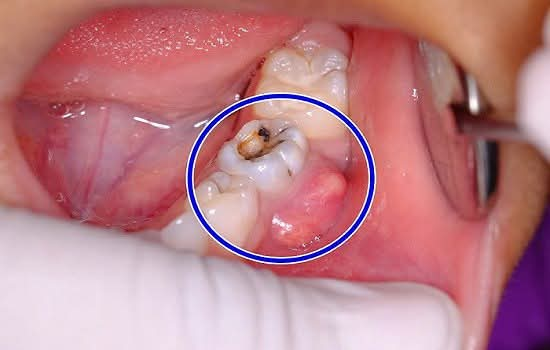

تعتبر مشاكل الفم والأسنان من المشاكل الصحيّة التي تصيب نسبة كبيرة من الناس، وإحدى هذه المشاكل هي خراج الأسنان والذي يصيب المناطق الموجودة تحديداً بين اللثة والأسنان،

أو يكون داخل جذور الأسنان نفسها وتنتج هذه المشكلة عن أسباب مختلفة من أبرزها تسوس الأسنان

إضافةً إلى العديد من المشاكل التي تصيب الأسنان كالكسور والتهابات اللثة، والصدمات المختلفة التي تتعرض لها الأسنان، .